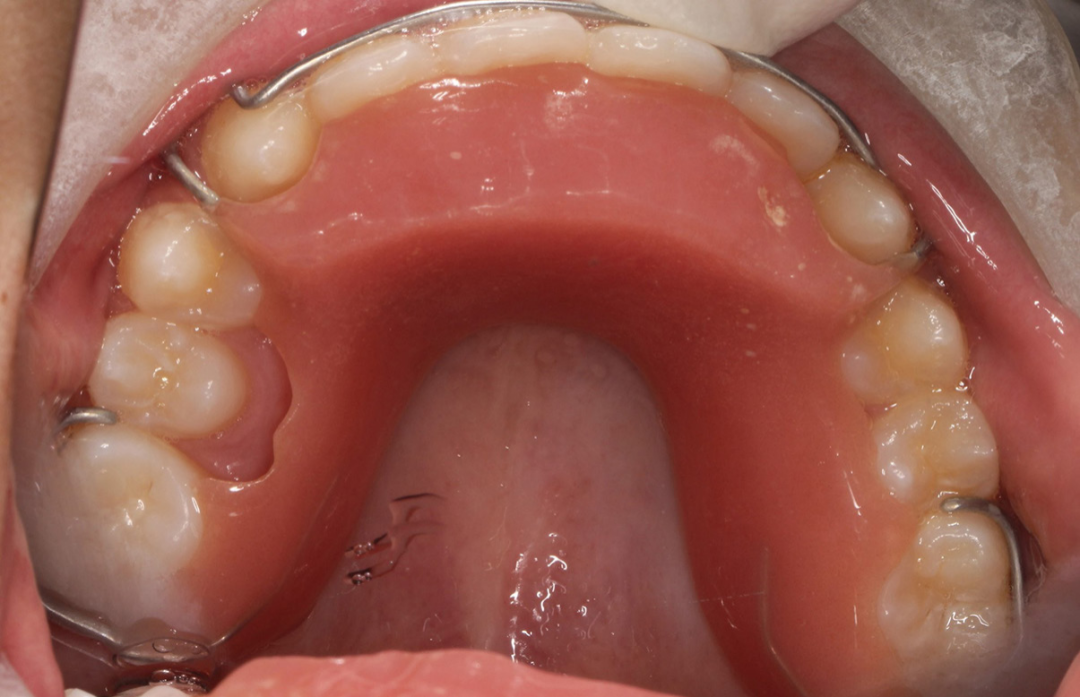

那么替牙期引导下颌向前的方法其实比较多,我们常用的有2x4口外弓、Twin Block、斜导工具、隐形牙套+II类颌间牵引、Activitor肌激动器、FrankelⅡ等。

另外我们比较过固定托槽矫治和无托槽矫治技术,现在大量的病例也在证明,整平下颌后部颌平面的效果,无托槽矫治器压低后牙整平下颌后部颌平面效果最好,做一些颌间牵引,同样可以引导下颌再前移,而且效果也会非常的好。

II类牵引是最有效的方式,无托槽矫治技术中的上下牙套去除了上下后牙的咬合接触, 因此去除了下颌后退的咬合锁结关系。

同时透明牙套对牙冠的全包裹固位方式产生足够大的力矩,对牙根的控制力更好,因此II类牵引能够有效地促进下颌前伸,通常我们使用狐狸或者兔子皮筋做II类牵引。总之,我觉得技术在不断的进步,在帮助孩子改善骨性下巴后缩问题的同时,选择适合孩子,且让孩子舒适的矫治器是很重要的。